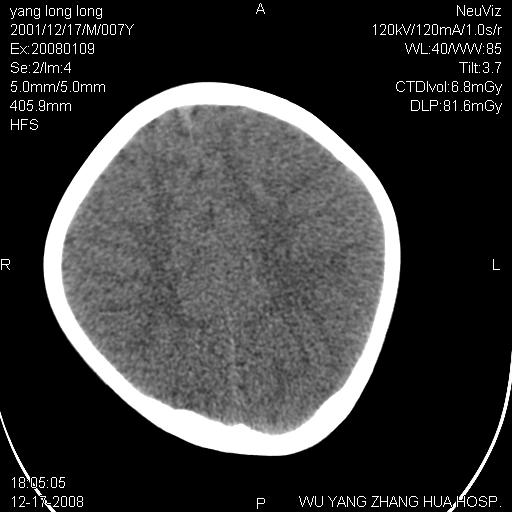

标题: PED1686:M7Y,头外伤,家人及自诉平时无任何不适。 [打印本页]

标题: PED1686:M7Y,头外伤,家人及自诉平时无任何不适。

考虑蛛网膜囊肿,请老师们看看多指导指导。

多考虑大枕大池。本例颅骨歪歪的,灶后枕骨似有膨胀征像(为蛛网膜囊肿征像),但整个左侧枕叶后方枕骨均有向后膨隆,所以暂不考虑蛛网膜囊肿。必要时随访